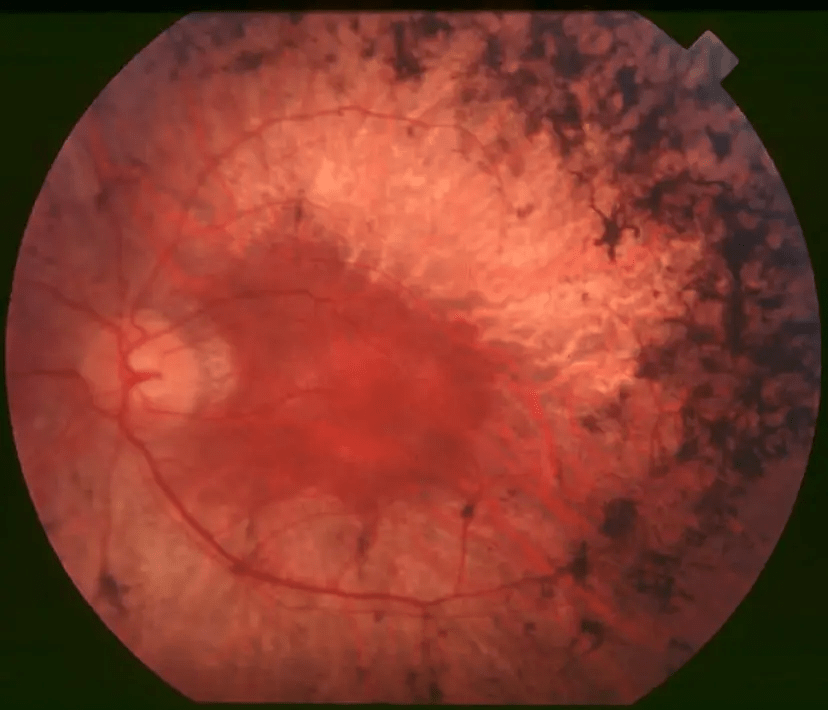

OPTOGENETİK

Retinitis Pigmentosa

Rodopsin temelli vektör kullanımı

Ölçüm Paradigması

Sahen et al. (2021)